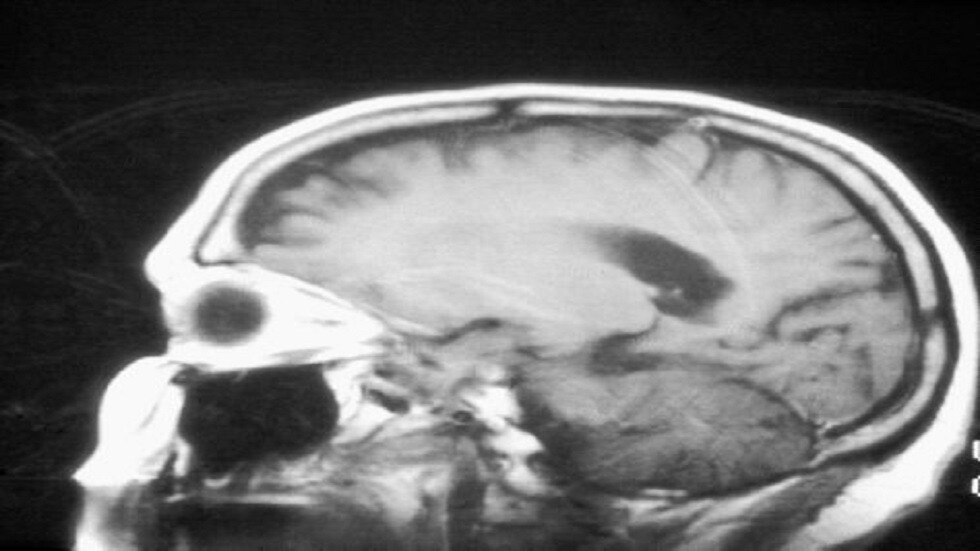

روسيا.. ابتكار طريقة جديدة لتدمير خلايا الورم في الدماغ

يقترح علماء معهد الأحياء والطب الحيوي بجامعة لوباتشيفسكي الروسية في نيجني نوفغورود، طريقة جديدة لتدمير خلايا أورام الدماغ، وتساعد على تحديد جرعة الإشعاع اللازمة.

ووفقا للمكتب الإعلامي للجامعة، "يعمل علماء معهد الأحياء والطب الحيوي على ابتكار عقار يمكنه تدمير خلايا أورام الدماغ، دون أن يؤثر في وظائفه. و يستبعد هذا العقار استخدام العلاج الضوئي المباشر في علاج أورام الدماغ الدبقية، الأكثر انتشارا ".

نتائج واعدة لاختبار أول لقاح مضاد لسرطان الدماغ

ويشير الباحثون، إلى أن نتائج دراسة مزارع الخلايا العصبية، أظهرت أن العلاج الضوئي الديناميكي للأورام الدبقية باستخدام عوامل بورفيرازين الضوئية تدمر الورم و الشبكات العصبية أيضا، ما يؤدي إلى فقدان وظائف الدماغ.

وتقول فيكتوريا توروبانوفا، الباحثة في مختبر معهد علوم الأعصاب بالجامعة، "استخدمنا تراكيز ضوئية مختلفة كافية لتدمير الأورام. ولكن اتضح أن هذه التركيزات تؤدي إلى موت الشبكات العصبية أيضا. لذلك كان علينا كشف هذه المشكلة، ونشر النتائج والاستمرار في البحث عن طرق جديدة لعلاج الأورام الدبقية".

وتشير الباحثة، إلى أنه يمكن استخدام العوامل الضوئية لتدمير الخلايا السرطانية في المختبر، التي ستشكل أساس لقاح لعلاج أورام الدماغ. كما يمكن استخدام البورفيرازين في علاج أنواع أخرى من الأورام التي تختلف في المنشأ والتمثيل الغذائي من خلايا الجهاز العصبي. وبالإضافة إلى ذلك، تساعد المحسسات الضوئية على تدمير الورم، وعلى تحديد الجرعة المطلوبة من الإشعاع.

ووفقا لفيكتوريا توروبانوفا، تستخدم طرق مختلفة في علاج الأورام السرطانية، لغالبيتها آثار جانبية، "لذلك نحن نعمل على الموت المناعي للخلايا السرطانية، الذي يتضمن استخدام قوى الجسم الطبيعية لمكافحة الأورام، واستثناء العلاج الكيميائي والإشعاعي. ومهمتنا التالية هي ابتكار لقاح مضاد للأورام الدبقية واختباره على الحيوانات المخبرية".